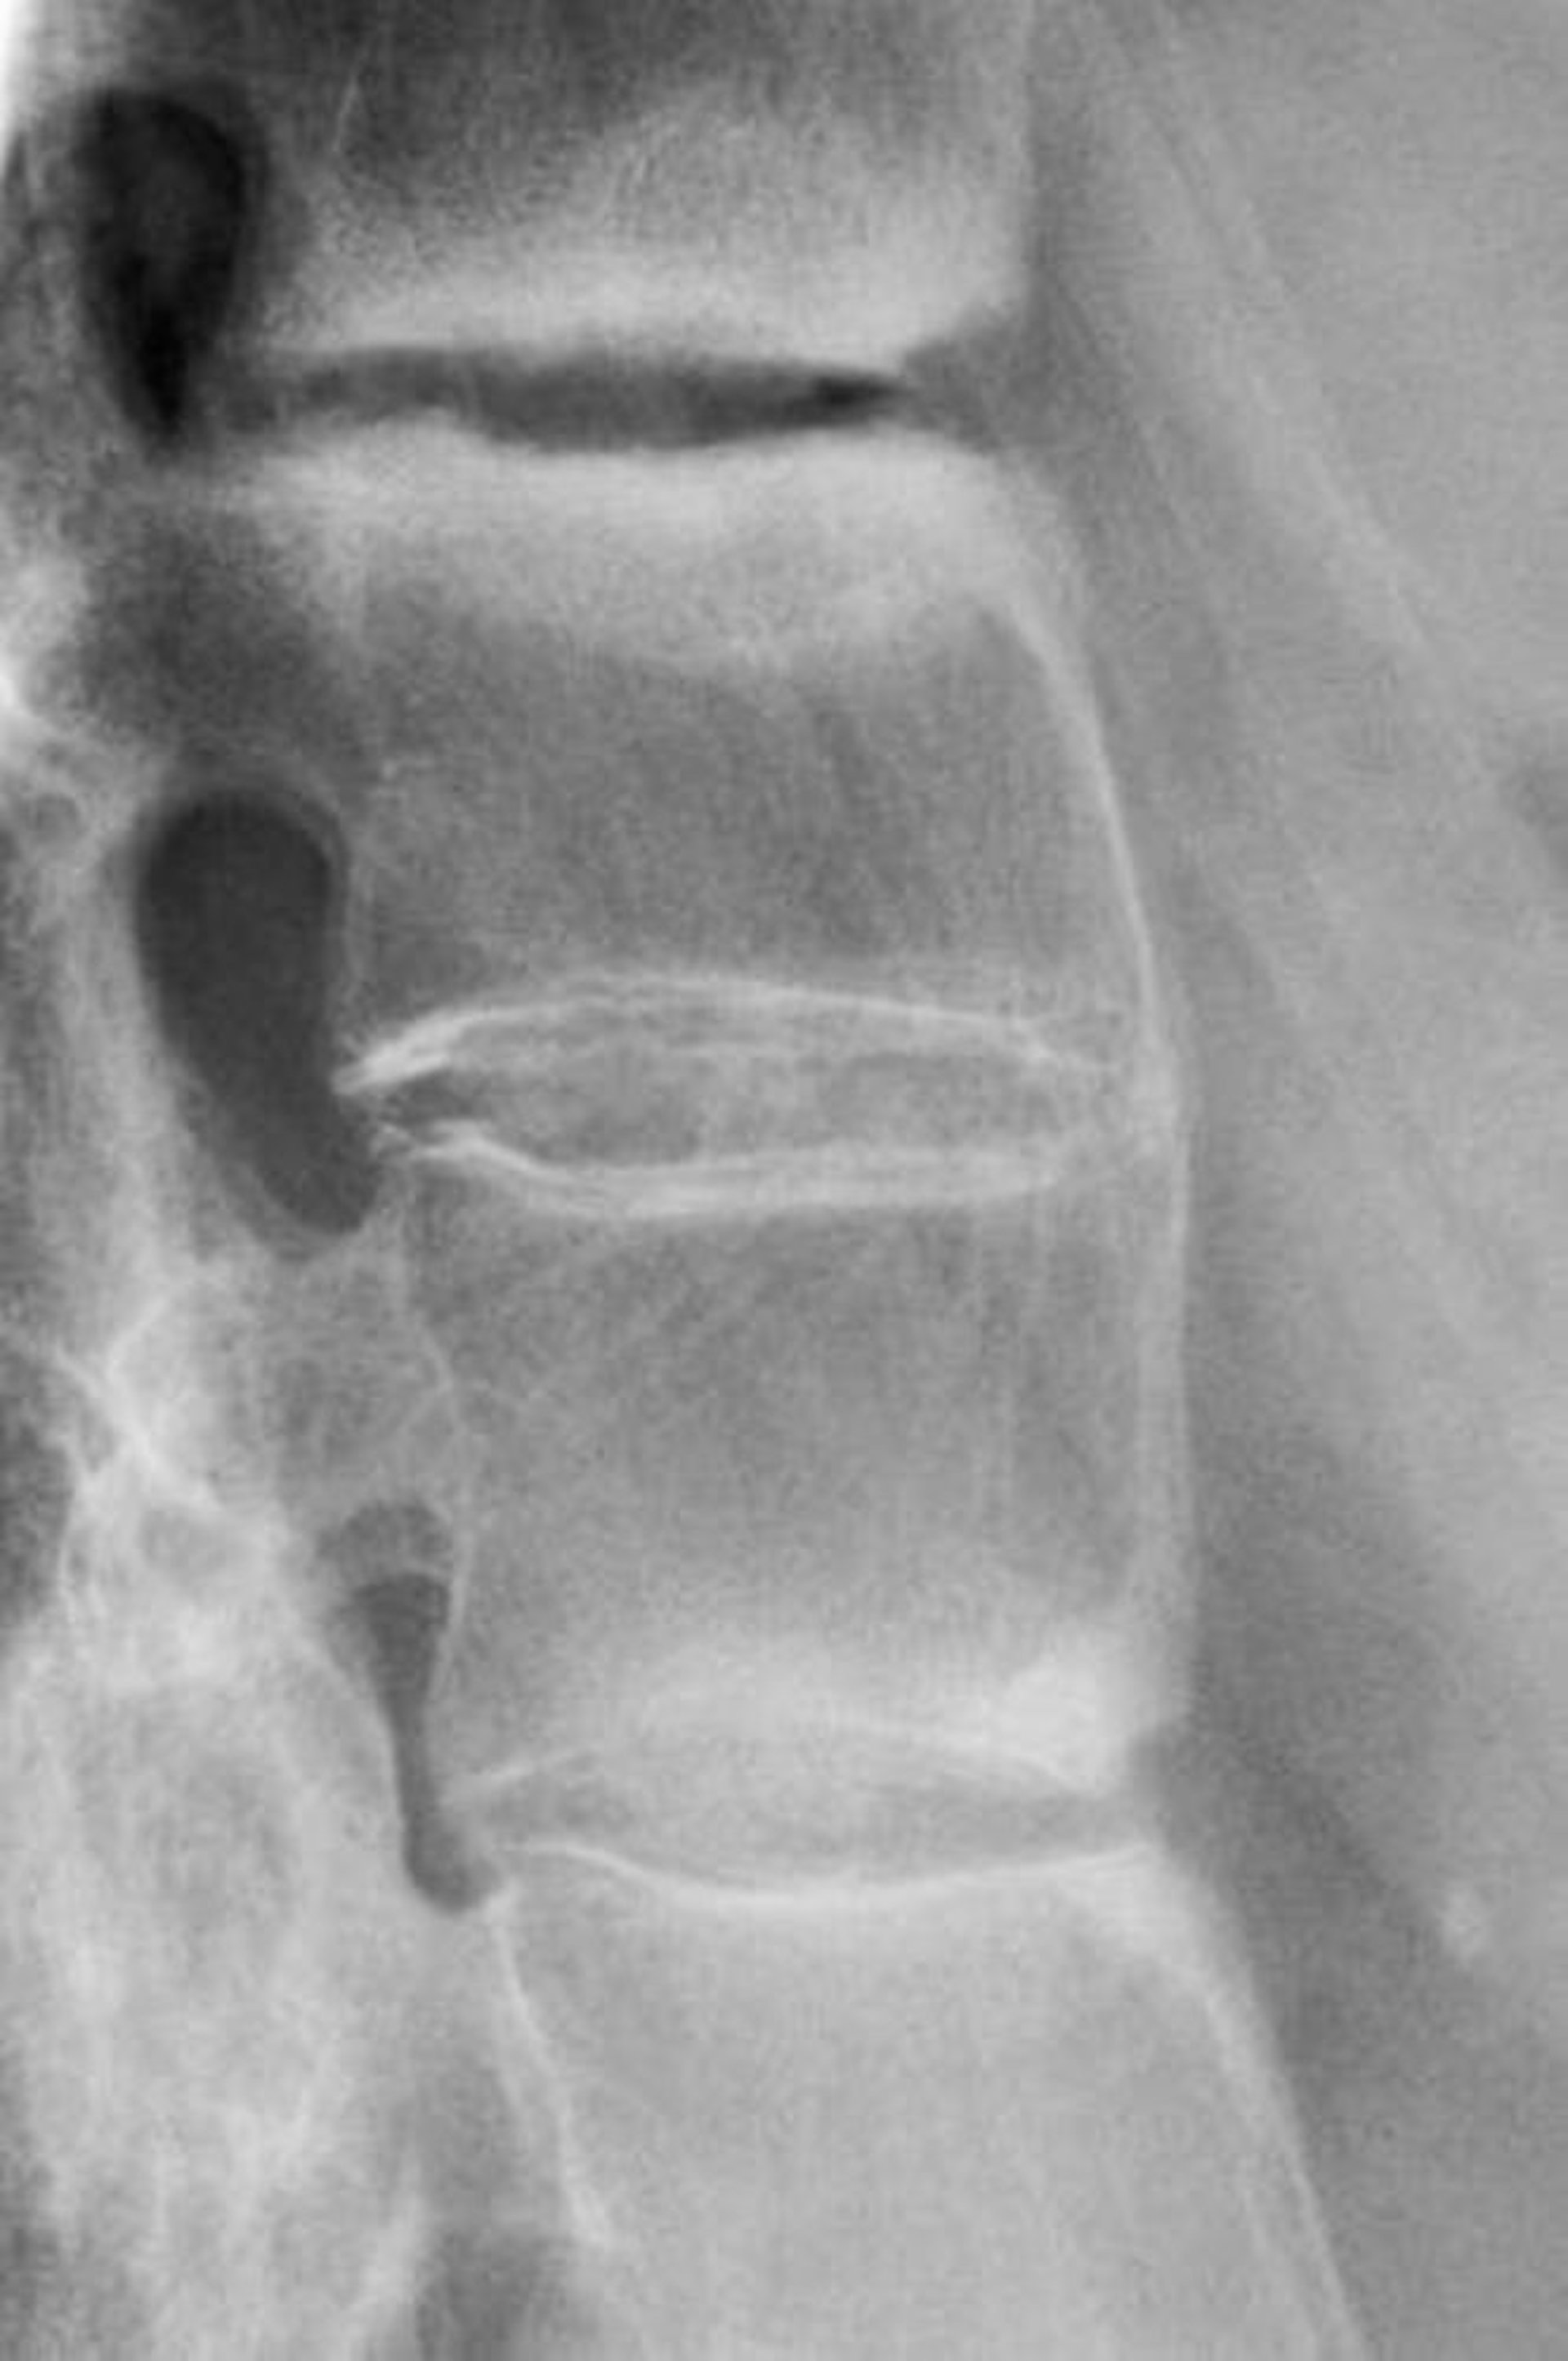

強直性脊椎炎

このX線写真には,腰椎間の硬化像,前弯の減弱,および腰椎の癒合という,進行した強直性脊椎炎を示唆する所見が認められる。

DR P. MARAZZI/SCIENCE PHOTO LIBRARY